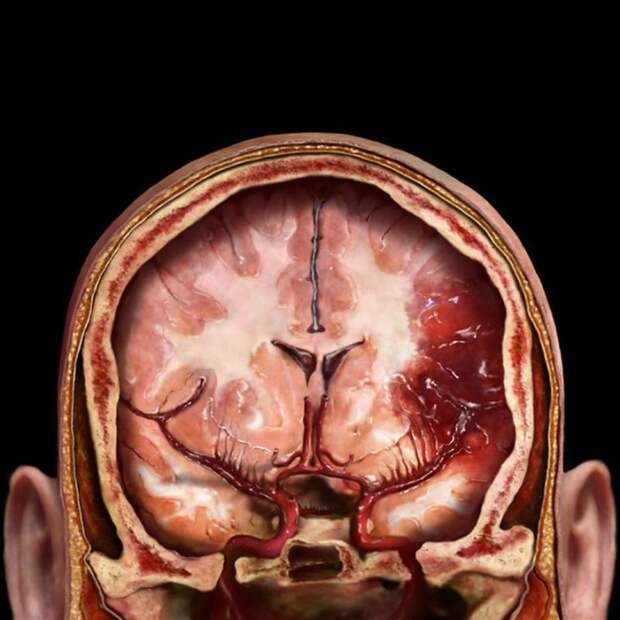

Вид мозга в черепной коробке